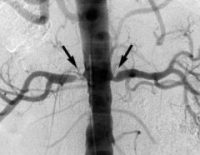

Томографическая рентгенография является наиболее точным методом диагностики. Ангиография дает трехмерное изображение почечных артерий и аорты, на которых отчетливо видны атеросклеротические бляшки. МР-ангиография почечной артерии рекомендуется для пациентов со сниженной СКФ.

Внутриартериальная цифровая субтрактивная ангиография дает точную морфологическую картину сосудов, пораженных атеросклерозом. Техника также используется для измерения артериального давления. Обследование в основном проводится при подготовке к хирургическому лечению.